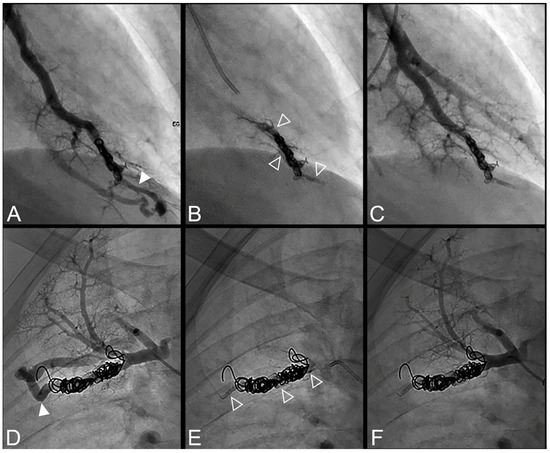

Figure 4.

Case example of an 18-year-old man treated for a complex recurrent pulmonary arteriovenous malformation in the middle lobe. Digital subtraction angiography unsubtracted images showed a recanalization in two different segmental feeder arteries (A–F). Embolization was performed using Onyx® (0.5 mL in each artery) to fill the afferent artery upstream and within the pre-implanted coiling and resulted in an immediate complete occlusion, maintained after 43 months follow-up. No leak in the aneurysm or in the vein was reported. (A). Opacification of an afferent artery (full head arrow) showed a recanalization through the pre-implanted coils. (B). Opacity upstream and in the last coil (empty arrowhead) showed the distribution of Onyx® without any evidence of a leak in the aneurysmal sac or proximal arterial branch. (C). Opacification of the afferent artery showed the absence of opacification of the aneurysmal sac and the efferent vein in favor of immediate occlusion. The opacification of the healthy arterial branch did not reveal any perfusion defect. (D). Opacification of a second afferent (full head arrow) artery showed a recanalization through the pre-implanted coils. (E). Opacity upstream of the coils showed a leak of Onyx® (empty arrowhead) without evidence of any leak in the aneurysmal sac. (F). Opacification of the afferent artery showed the absence of opacification of the aneurysmal sac and the efferent vein in favor of immediate occlusion. The opacification of the healthy arterial branch did not reveal any lung perfusion defect.